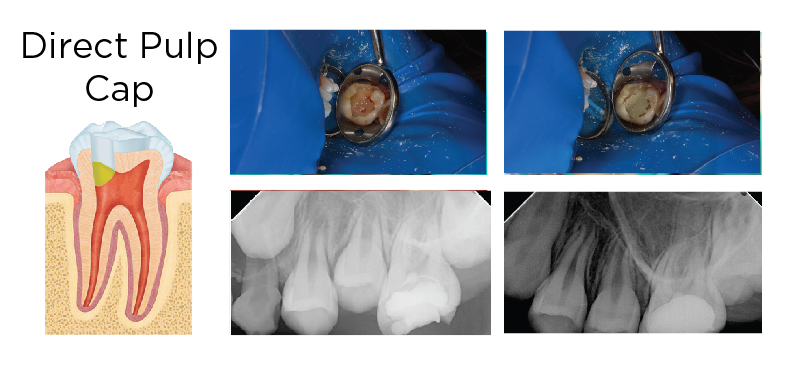

MTA AS A DIRECT PULP CAP

Fig. 2. A deep carious lesion was diagnosed with reversible pulpitis on a permanent molar treated with complete caries removal (upper left). The pulp was exposed and treated with sodium hypochlorite, and a layer of MTA was placed (upper right). The tooth was temporized (lower left) and restored with a resin composite (Premise) at a later date. At two-year recall, the tooth remains asymptomatic and shows no signs of apical pathology (lower right).